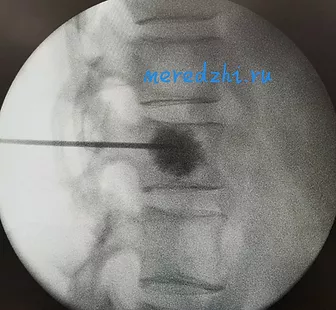

Операция осуществляется под контролем рентгеновской аппаратуры в двух проекциях, что позволяет точно определять расположение костного цемента в теле позвонка.

Рентген-контроль введения и распределение костного цемента (боковая и прямая проекции)